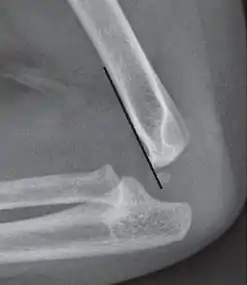

Anterior humeral line - It is a line drawn down along the front of the humerus on the lateral view and it should pass through the middle third of the capitulum of the humerus.[9] If it passes through the anterior third of the capitulum, it indicates the posterior displacement of distal fragment.[8]

The anterior humeral line is not reliable in children with sparse ossification of the capitulum, such as in this 6 months old child.[9]